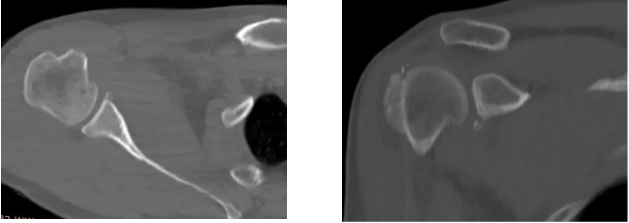

病例1

病史摘要:男性,44歲,跌傷致右肩關(guān)節(jié)疼痛數(shù)天,活動(dòng)不利。

CT圖示:右側(cè)肱骨后外上方局部骨皮質(zhì)塌陷,連續(xù)性中斷(箭頭);肩胛盂前下份邊緣變鈍,見高密度分離小骨片影(三角形)。